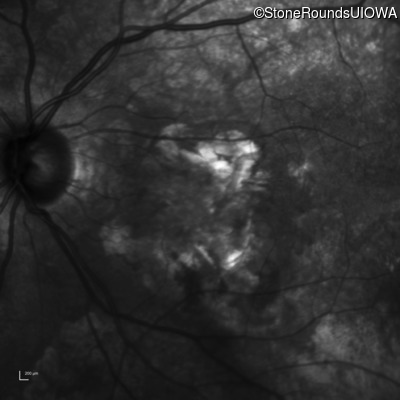

Infrared Fundus Photograph - Left - 20/160 -1

Exemplar